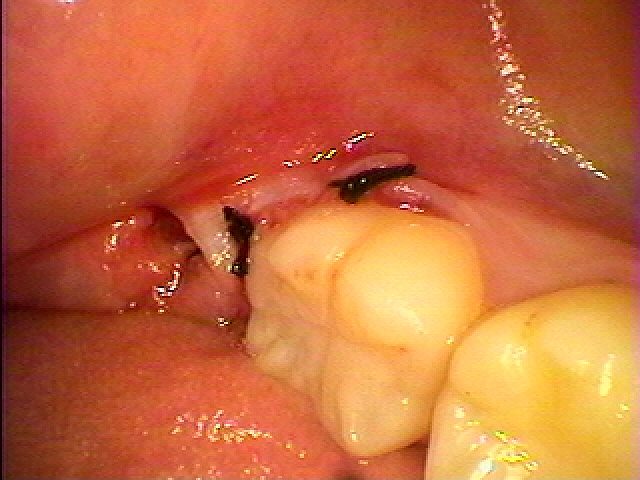

左下奥の完全埋伏歯の難抜歯 時々腫れる 近くの歯医者にて抜歯を行った方がよいといわれた|お知らせ |広島市安佐南区の歯科医院 左下奥の完全埋伏歯の難抜歯 時々腫れる 近くの歯医者にて抜歯を行った方がよいといわれた トップ お知らせ・ブログ お知らせ 左下奥の完全埋伏歯の難抜歯 時々腫れる 近くの歯医者にて抜歯を行った方がよいといわれた 左下奥の完全埋伏歯の難抜歯 時々腫れる 近くの歯医者にて抜歯を行った方がよいといわれた 問題の歯は見えません ここに親知らずが埋まっています パノラマになります 最小限で開けていきました 歯冠部を分割抜歯を行っていきました 根部を取りでしていきます 縫合して終了となります 綺麗に抜歯できました Web診療予約 初めての方へ 選ばれ続ける理由 院内設備について 歯が痛いしみる一般歯科 歯がぐらぐらする歯周病 健康な歯を保ちたい予防歯科 子供の虫歯予防をしたい小児歯科 銀歯をセラミックに審美歯科 白い歯を目指しませんか?ホワイトニング 矯正専門医がいるので安心矯正歯科 抜けた歯を補いたいインプラント・入れ歯 医院案内 スタッフ紹介 メリィハウス歯科クリニックオフィシャルホームページ ラベンダー歯科クリニックオフィシャルホームページ お知らせ・ブログ ホーム 診療科目 一般歯科 歯周病治療 予防治療 小児歯科 審美治療 ホワイトニング 矯正歯科 入れ歯・インプラント マウスピース矯正 初めての方へ 院長・スタッフ 設備紹介 医院案内・アクセス メニューを閉じる